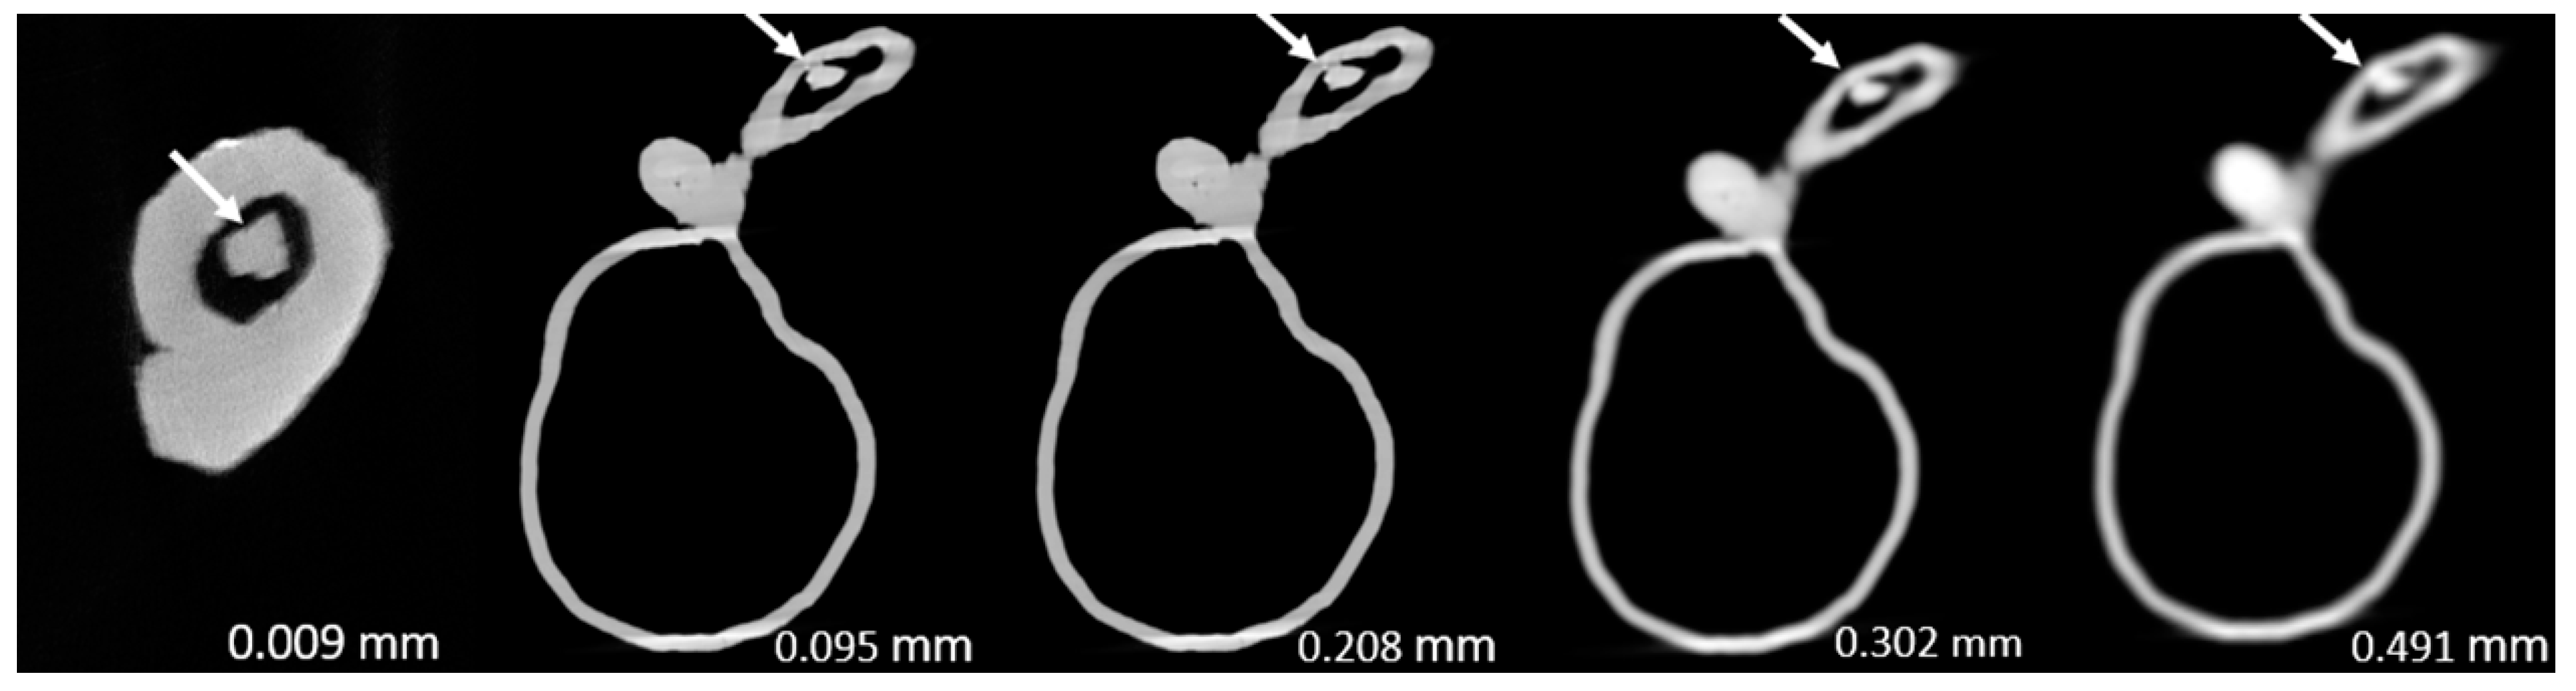

Figure 3, Figure 4, Figure 5, Figure 6, Figure 7 and Figure 8 show the micro-CT and SRCT images of plaques 1 and 2 in models 1-3 that were used for the stenosis assessments. For the micro-CT (0.009 mm slice thickness) images, only the stenotic areas were illustrated due to the processing power limit of the workstation for handling data with a very large matrix (7872×7872). The micro-CT (0.009 mm slice thickness) images were able to clearly demonstrate patent areas between the calcification and the left coronary arterial walls, especially in severe stenosis compared with SRCT (0.095-0.491 mm slice thickness) images (Figure 3, Figure 4 and Figure 5 with >90% stenosis).

Figure 8. Two-dimensional micro-computed tomography (micro-CT) (0.009 mm slice thickness) and synchrotron radiation CT (0.095-0.491 mm slice thickness) images of plaque 2 in model 3 causing 70% stenosis (reprint of synchrotron radiation CT images with permission [15]).